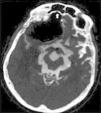

Spontaneous pneumocephalus following cerebrospinal fluid shunt is a rare complication. In most cases, the air enters in the intracranial cavity via a skull base defect. We report 2 cases of delayed tension pneumocephalus, secondary to ventriculoperitoneal shunt, and review the etiopathogenesis, prevention and treatment of this condition.